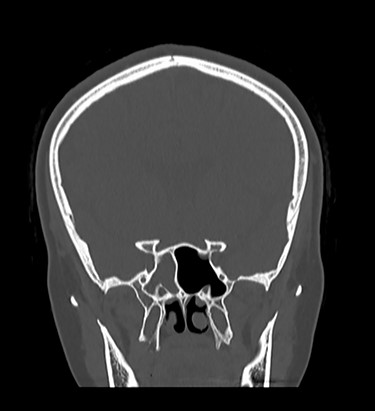

Patient underwent sinus computed tomography (CT), which demonstrated opacification of the right sphenoid sinus (Fig. 2). Brain MRI showed possible cerebrospinal fluid (CSF) leak at the right sphenoid sinus (Fig. 3). Lumbar puncture was done and fluid sent for analysis to rule out meningitis.

Coronal MRI of brain, T2 weighted image, showing opacification of right sphenoid sinus.